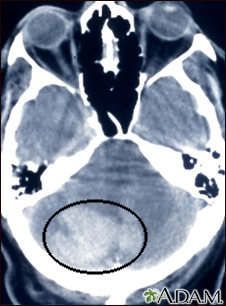

Intracerebellar hemorrhage - CT scan